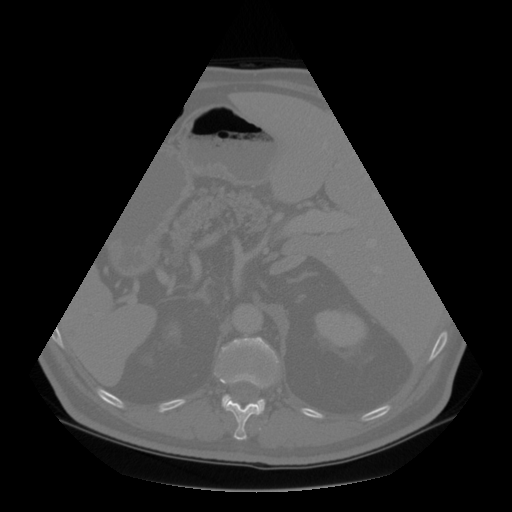

Fig. 5 and 6 present examples of the translation results from CT to ultrasound. These visual comparisons demonstrate that the S-CycleGAN can not only mimic the ultrasound style but also preserve critical anatomical features compared with Fig. 3. The synthetic images closely resemble real ultrasound scans in terms of texture and shape, suggesting a high level of detail preservation.

Refer to caption

(a) Real CT

(b) Fake US

(c) CT Label

(d) Predicted US Mask

Figure 6: CT-to-ultrasound translation example.2